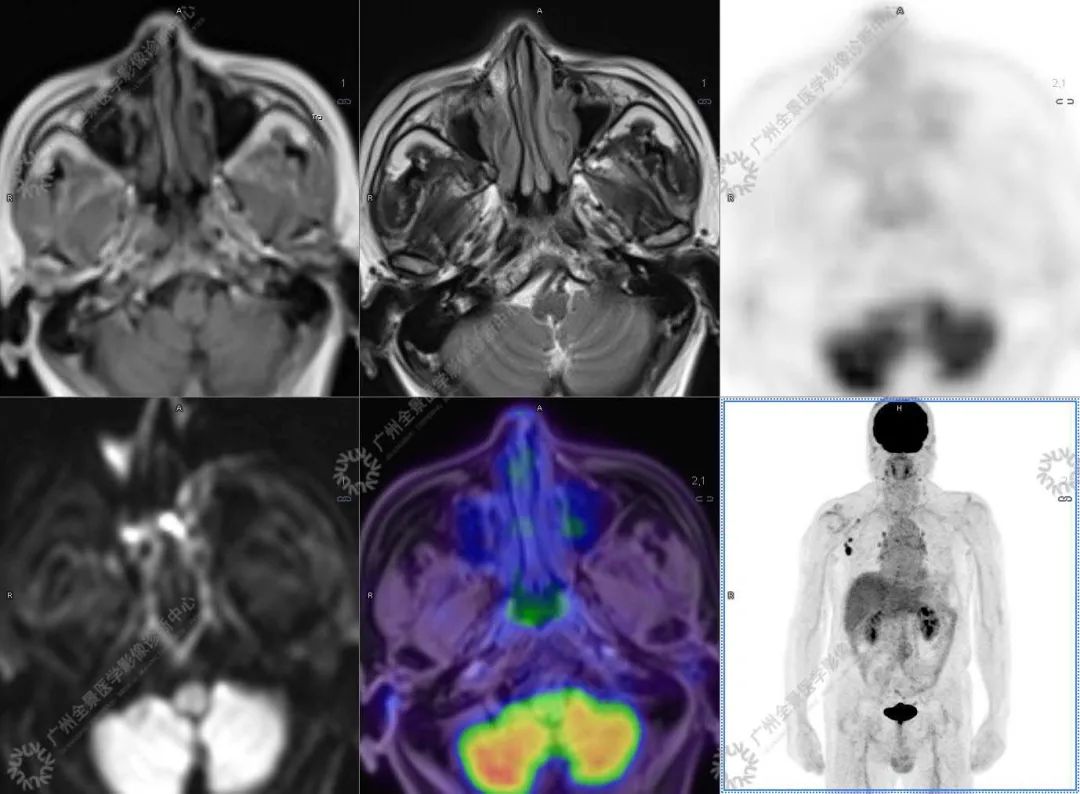

结合影像及实验室检查,临床最终考虑 IgG4 相关性疾病。

●18FDG-PET/CT 作为一种解剖和功能结合新的显像方法,IgG4-RD 的诊断及鉴别诊断中存在着巨大的优势:

●18FDG-PET/CT 扫描作为一种全身检查,有着传统影像学局部扫描无法比拟的优势,PET/CT 扫描不仅可以发现以临床症状为导向的局部病灶,更可以发现远隔部位的受累病灶。